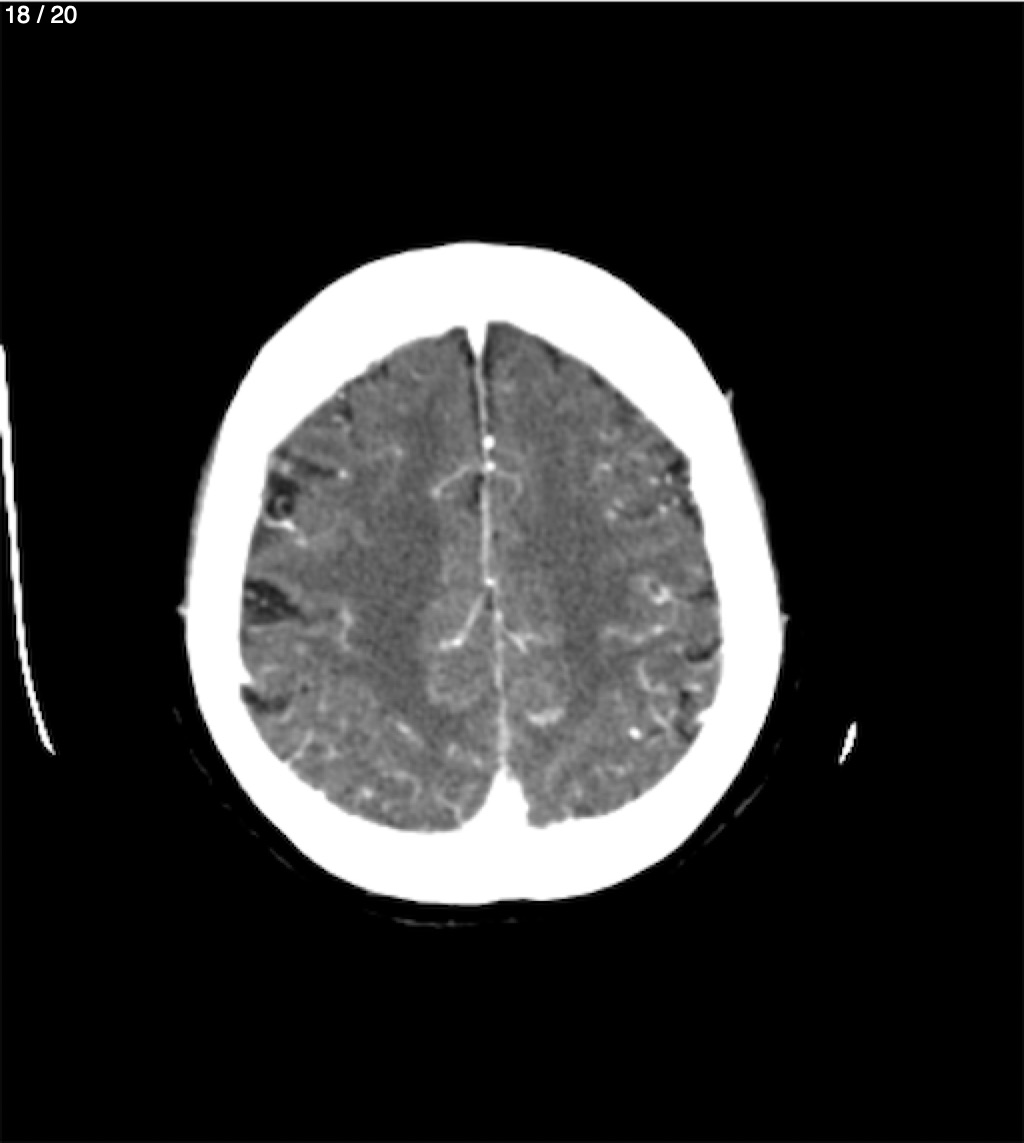

Jose Sosa Martinez 66A - Angiotac Craneo